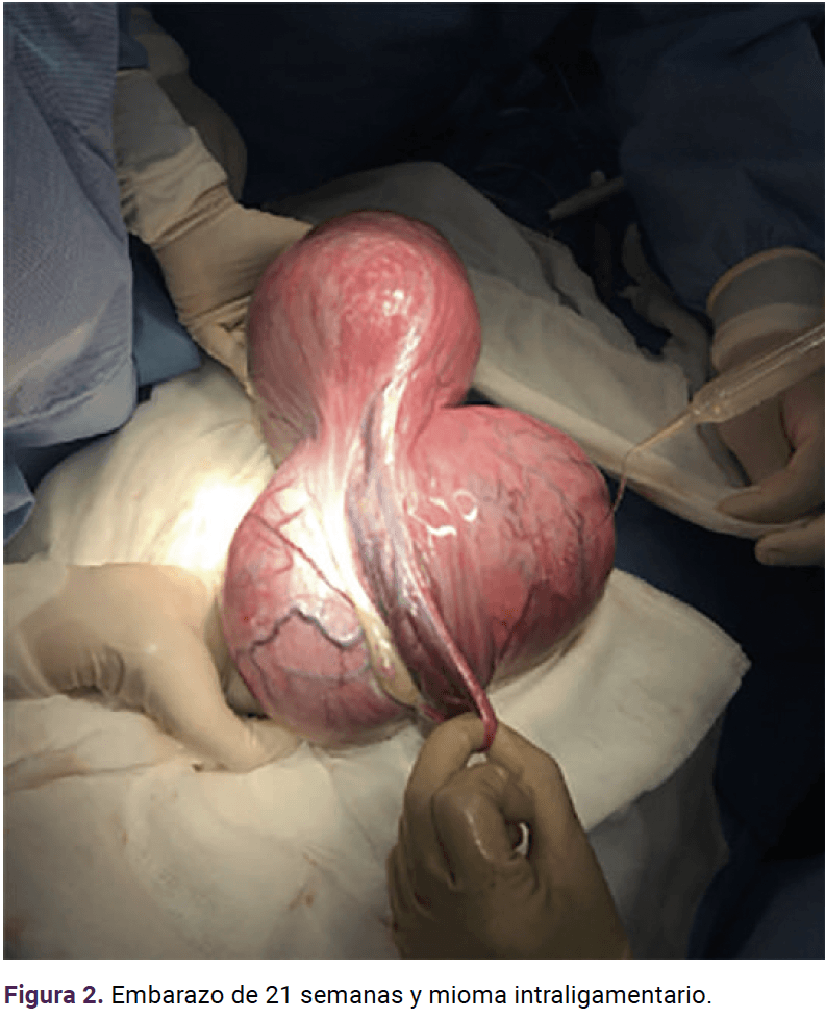

Paciente de 19 años, primigesta, con antecedente heredofamiliar (tía paterna) de cáncer de ovario. Acudió a consulta para control prenatal a las siete semanas de gestación, con dolor abdominal y crecimiento rápido de un tumor abdominal. Durante la exploración física el abdomen se palpó globoso, a expensas del tumor abdominopélvico, a 2 cm por arriba de la cicatriz umbilical, móvil, con dolor a la palpación media y profunda. El ultrasonido reportó un mioma subseroso de 15.4 x 7.3 cm y la resonancia magnética concluyó que se trataba de un mioma con diámetro mayor de 24 centímetros que desplazaba y comprimía la cavidad amniótica (Figura 1). En la interconsulta con el ginecooncólogo se planteó la posibilidad de complicaciones conforme el mioma fuera creciendo; por ello se decidió la miomectomía abierta en el segundo trimestre de la gestación. La miomectomía se llevó a cabo, sin ingreso a la cavidad uterina, a las 21.4 semanas y se extirpó un mioma intraligamentario de 20 x 18 x 11 cm y 2410 g (Figuras 2, 3 y 4) con sangrado de 900 mL y las dificultades propias de un mioma hipervascularizado. El estudio transoperatorio reportó: leiomioma con cambios hidrópicos, negativo para malignidad (mismo diagnóstico del reporte definitivo). Se finalizó el procedimiento y se corroboró la frecuencia cardiaca fetal de 150 lpm. El resto del control prenatal transcurrió sin complicaciones y se finalizó el embarazo a las 38.0 semanas mediante cesárea, indicada por registro cardiotocográfico categoría II (línea basal con bradicardia con mínima variabilidad y ausencia de aceleraciones), sin complicaciones, con sangrado de 300 mL y obtención de una recién nacida de 2515 g, Apgar 8-9. A petición de la paciente se le colocó un dispositivo intrauterino de levonorgestrel, como método de control de la fertilidad.

<strong>Figura 2</strong>

Figura 2.